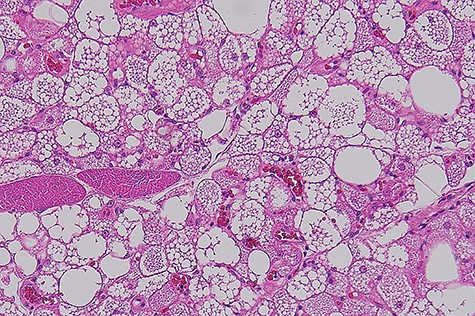

Macroscopically, it was a fatty mass measuring 48 × 39 × 35 mm, which on cross-section did not reveal any necrosis, haemorrhagic or fibroseptae formation. Microscopically the lesion was composed of lobules of brown far with abundant macrovesicles (Fig. 2). There was no evidence of increased mitotic activity or necrosis. There were no infiltrative borders on the lesions. Fluorescence in situ hybridization was used for assessment of MDM2 gene (12q15) amplification, which was negative. This was performed to rule out any atypical lipomatous tumour.

Histophotograph showing lobules of fat with multivaculated brown fat cells without evidence of dysplasia or necrosis.

Hibernomas are typically fatty hypervascular lesions that are grossly similar to lipomas. They are well-defined, encapsulated mobile masses. The colour varies from tan to red-brown, depending on the amount of intracellular lipid. While adult adipocytes have an eccentrically placed nucleus within a clear cytoplasm, hibernoma has a central nucleus with a multivacuolated and granular eosinophilic cytoplasm [1].

Four morphologic variants of hibernoma have been identified: typical (82%), myxoid (8%), lipoma like (7%) and spindle cell [2]. The present case belongs to the typical variant as evident by eosinophilic cells multivacuolated. The myxoid variety has a high water content; the lipoma-like variant contains significant amounts of adult fat and commonly affects the thigh. Finally, the spindle cell variant has features of spindle cell lipoma and hibernoma and occurs primarily in the subcutaneous tissues of the neck [5]. There is no size-based classification been established. All the morphologic variants follow a benign course and should be removed completely. The follow-up of 66 cases over a mean period of 7.7 years (range, 6 months and 28 years) showed no recurrence or metastasis, including eight cases of intramuscular tumours [2, 4].